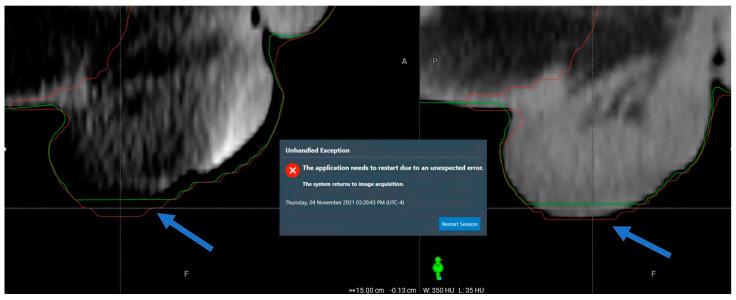

Cone-beam computed tomography (CBCT)-guided online adaptive radiotherapy (oART) represents a significant advancement in radiation oncology, enabling on-couch plan adaptation to account for daily anatomical changes. While this automation improves precision and workflow efficiency, it also introduces new failure modes (FMs) and workflow irregularities. This study aimed to systematically evaluate the clinical and technical challenges associated with CBCT-guided oART implementation. We retrospectively analyzed over 1000 CBCT-guided oART sessions for pelvic malignancies performed at our institution. A multidisciplinary team conducted a comprehensive review to identify and classify FMs, followed by root cause analysis (RCA) to evaluate their impact on treatment safety, efficacy, and workflow robustness. In addition to session-terminating FMs, we identified recurring failure modes across three major domains: (1) system-driven issues, such as rigid target localization and software-driven irregularities; (2) patient-driven challenges, including interfractional and intrafractional anatomical variations; and (3) treatment planning and execution failures, including excessive dose hotspots from field-of-view limitations. The system's closed-loop automation, while streamlining processes, introduced rigid constraints in plan adaptation and fallback plan execution, occasionally leading to unintended dose discrepancies. This study provides a comprehensive clinical practice-based evaluation of CBCT-guided oART, highlighting system-specific failure modes and their implications. Addressing these challenges requires structured quality assurance processes, multidisciplinary collaboration, and continuous workflow refinement. Our findings contribute to the development of safer and more robust adaptive radiotherapy platforms and clinical workflows.

锥形束计算机断层扫描(CBCT)引导的在线自适应放射治疗(oART)是放射肿瘤学的一项重大进展,能够在治疗床上对计划进行调整,以适应每日的解剖结构变化。虽然这种自动化提高了精度和工作流程效率,但也引入了新的故障模式(FMs)和工作流程异常情况。本研究旨在系统评估与CBCT引导的oART实施相关的临床和技术挑战。我们回顾性分析了在我们机构进行的1000多例针对盆腔恶性肿瘤的CBCT引导的oART治疗疗程。一个多学科团队进行了全面审查,以识别和分类故障模式,随后进行根本原因分析(RCA),以评估它们对治疗安全性、疗效和工作流程稳健性的影响。除了导致疗程终止的故障模式外,我们还在三个主要领域识别出了反复出现的故障模式:(1)系统驱动的问题,如刚性靶区定位和软件驱动的异常情况;(2)患者驱动的挑战,包括分次间和分次内的解剖结构变化;(3)治疗计划和执行失败,包括由于视野限制导致的过量剂量热点。该系统的闭环自动化在简化流程的同时,在计划调整和备用计划执行方面引入了刚性约束,偶尔会导致意外的剂量差异。本研究基于临床实践对CBCT引导的oART进行了全面评估,突出了特定系统的故障模式及其影响。应对这些挑战需要结构化的质量保证流程、多学科协作以及持续的工作流程优化。我们的研究结果有助于开发更安全、更稳健的自适应放射治疗平台和临床工作流程。